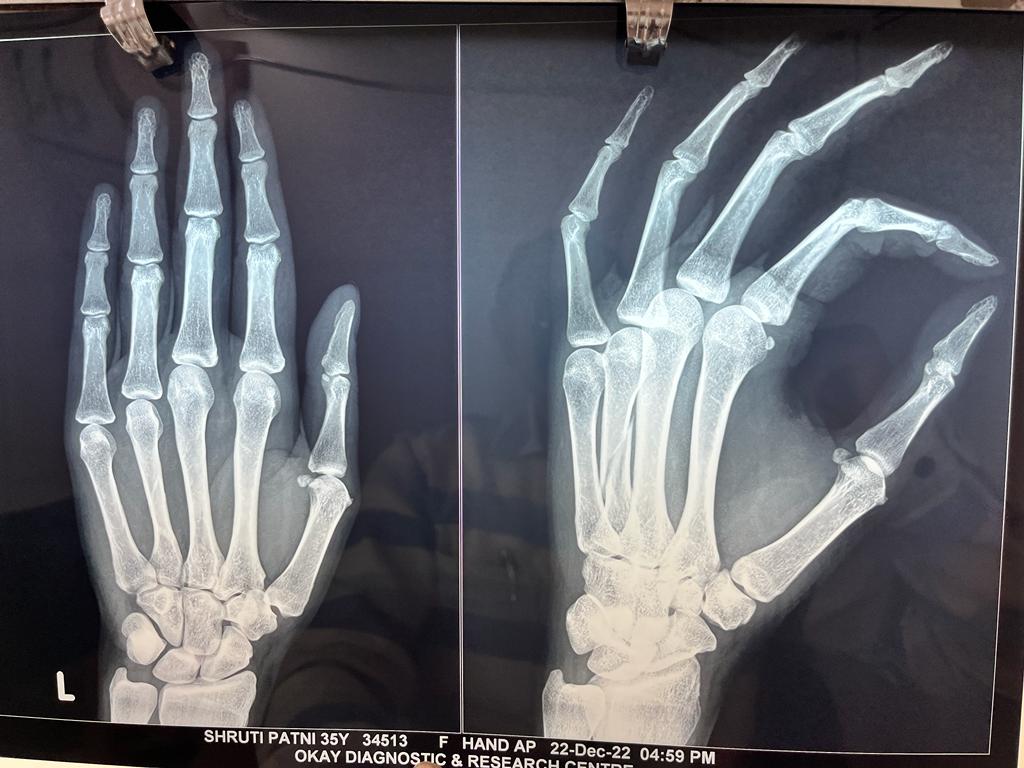

Pre and post of pics of 3 months old fracture 4 th metacarpal with pain shortening of finger and loss of knuckle prominence